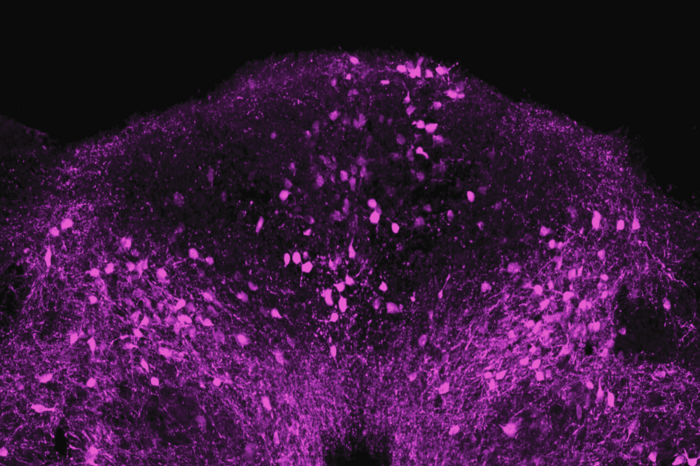

The team began by exposing mice to LPS, a piece of bacterial cell wall that activates the immune system and potently induces sickness behavior. Shortly after an injection of LPS, there was a spike in activity in a brainstem region known as the dorsal vagal complex, among a population of neurons expressing the neuropeptide ADCYAP1. To confirm that they had found the right brain cells, the researchers then activated those neurons in healthy mice and they found that the animals ate, drank, and moved around less. In contrast, when the ADCYAP1 neurons were deactivated , the effect of LPS on these behaviors was significantly reduced.

“We didn’t know if the same or different neurons regulated each of these behaviors,” Friedman says, “We found it surprising that a single neuronal population appears to regulate each of these components of the sickness response.”

The authors were not, however, altogether surprised that this brainstem region was involved in mediating sickness behaviors. The dorsal vagal complex is one of a precious few physiological crossroads of the central nervous system, where an absence of the blood brain barrier enables circulating factors in the blood to pass information directly to the brain. “This region has emerged as a kind of alert center for the brain, conveying information about aversive or noxious substances that, more often than not, reduce food intake,” Friedman says.